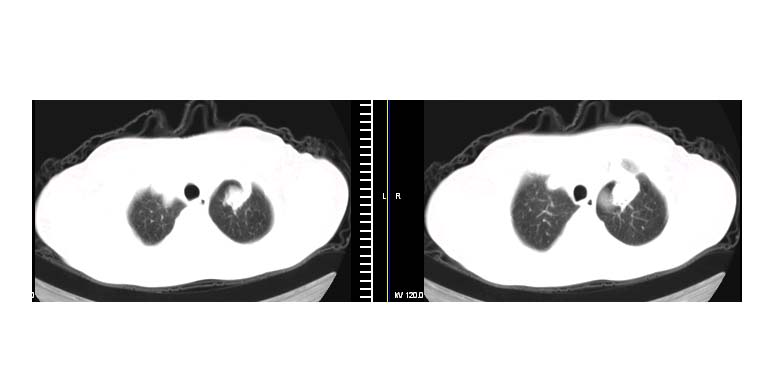

标题: CT11087:男性,82.咳嗽一周.抗炎治疗4-5天效果不明 [打印本页]

标题: CT11087:男性,82.咳嗽一周.抗炎治疗4-5天效果不明

左肺上叶尖段周围型肺癌伴左肺门淋巴结转移。

左上肺实质性肿块,浅分叶 毛糙 胸膜凹陷征 纵隔淋巴结肿大——支持:左肺上叶周围型肺癌!

左上肺软组织肿块,有分叶,短毛刺,气管旁间隙见有肿大淋巴结,考虑左上周围型肺癌伴纵隔淋巴结转移。

左肺上叶前段肺癌并纵隔淋巴结肿大。